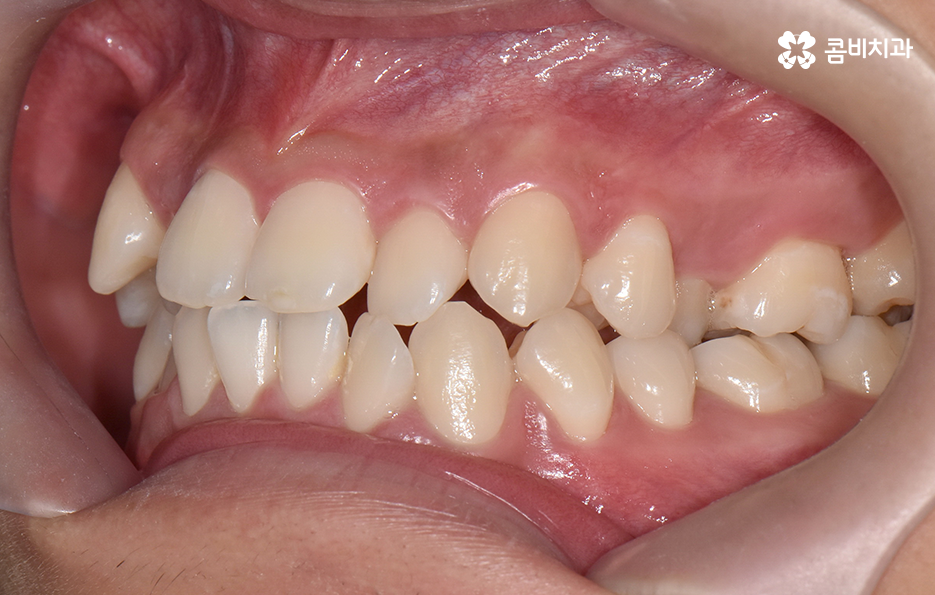

오늘 포스팅에서 보여지는 사진에서는 비발치 교정으로 덧니 교정이 가능했던 사례입니다. 덧니 교정 사례에서 발치교정 케이스는 흔한 치료 방법이긴 하지만 발치에 대한 판단은 치열만이 아니라 골격과 얼굴형을 종합적으로 고려하여 판단하고 치아를 얼마나 이동시켜야 할지 예측하여 판단하기 때문에 3D CT 등의 첨단 장비를 통한 검진과 경험 많은 교정 전문의와 충분히 상의하고 결정해야 합니다

치아교정은 치열을 가지런하게 재배열하는 치료이면서 각 개인의 얼굴형과 골격, 입술라인 등을 종합적으로 고려해야 하기 때문에 발치교정의 필요 여부를 판단하는 것에도 신중한 판단이 필요한데요

30대 치아교정 되도록 빨리 치료가 끝나길 원하시는 분들이 많겠지만 교정 치료는 결과가 중요한 치료이기 때문에 자신에게 적합한 치료 계획을 정교하게 세우는 것이 중요하며 발치는 한번 하면 되돌릴 수 없고 반대로 비발치 교정을 한다고 해도 치료상의 편의성만을 따지는 것이 아니라 결과가 중요하기 때문에 각 환자분들의 얼굴에 잘 어울리는 결과를 얻기 위해서는 비발치 교정이 얼마나 적합한지를 잘 따져봐야 하겠습니다

종합하면 발치교정의 필요성은 얼굴과의 조화, 골격 그리고 교합 등을 전체적으로 고려하여 판단하기 때문에 각 환자분들이 필요한 치아의 이동 정도를 정확히 예측하고 필요한 치아 이동 공간을 확보함에 있어서 발치교정이 적합할지 아니면 비발치적인 방법으로도 치아 이동 공간이 확보 가능한지 따져보고 있으며 발치교정이 아니더라도 치간삭제, 악궁확장, 어금니 후방이동과 같은 방법으로 공간 확보가 가능하기 때문에 각 환자분들에게 적합한 1:1 맞춤형 치료가 진행되고 있어요